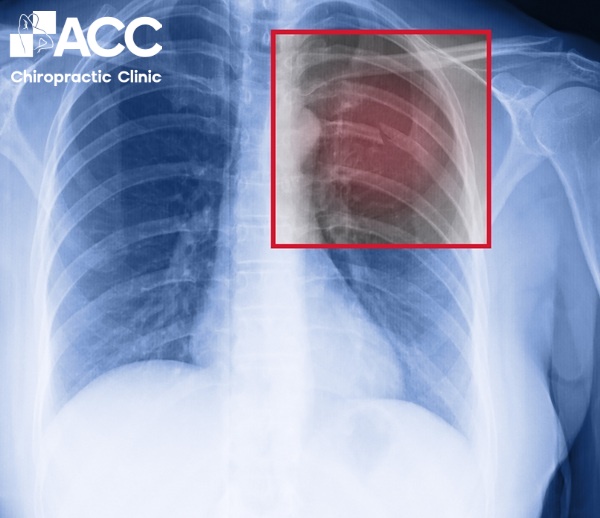

2.2 Trật xương sườn

Tai nạn, ngã, chấn thương hoặc áp lực lớn có thể khiến xương sườn bị lệch khỏi vị trí. Khi xương sườn bị trật có thể xuất hiện các cơn đau dữ dội lan sang vùng bả vai và lưng khiến bạn khó khăn trong việc vận động, một số trường hợp còn bị khó thở.